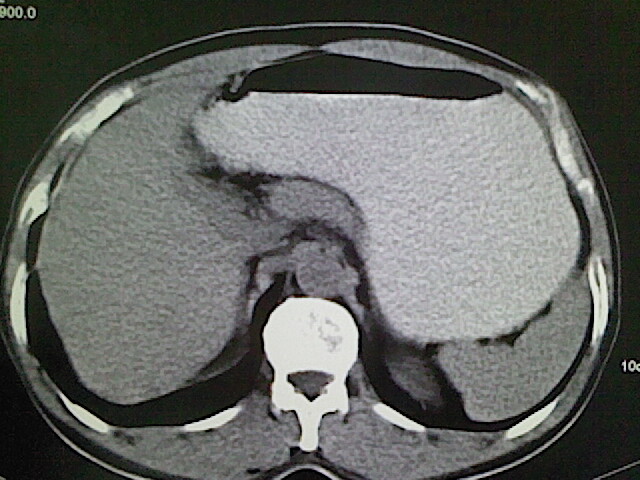

标题: CT18630:男,54岁,乙肝,大家看怎么样? [打印本页]

男,54岁,乙肝,大家看怎么样?

肝脏的要有增强敢说话

未见明确异常;建议必要时行ct增强扫描检查。

平扫未见明显异常